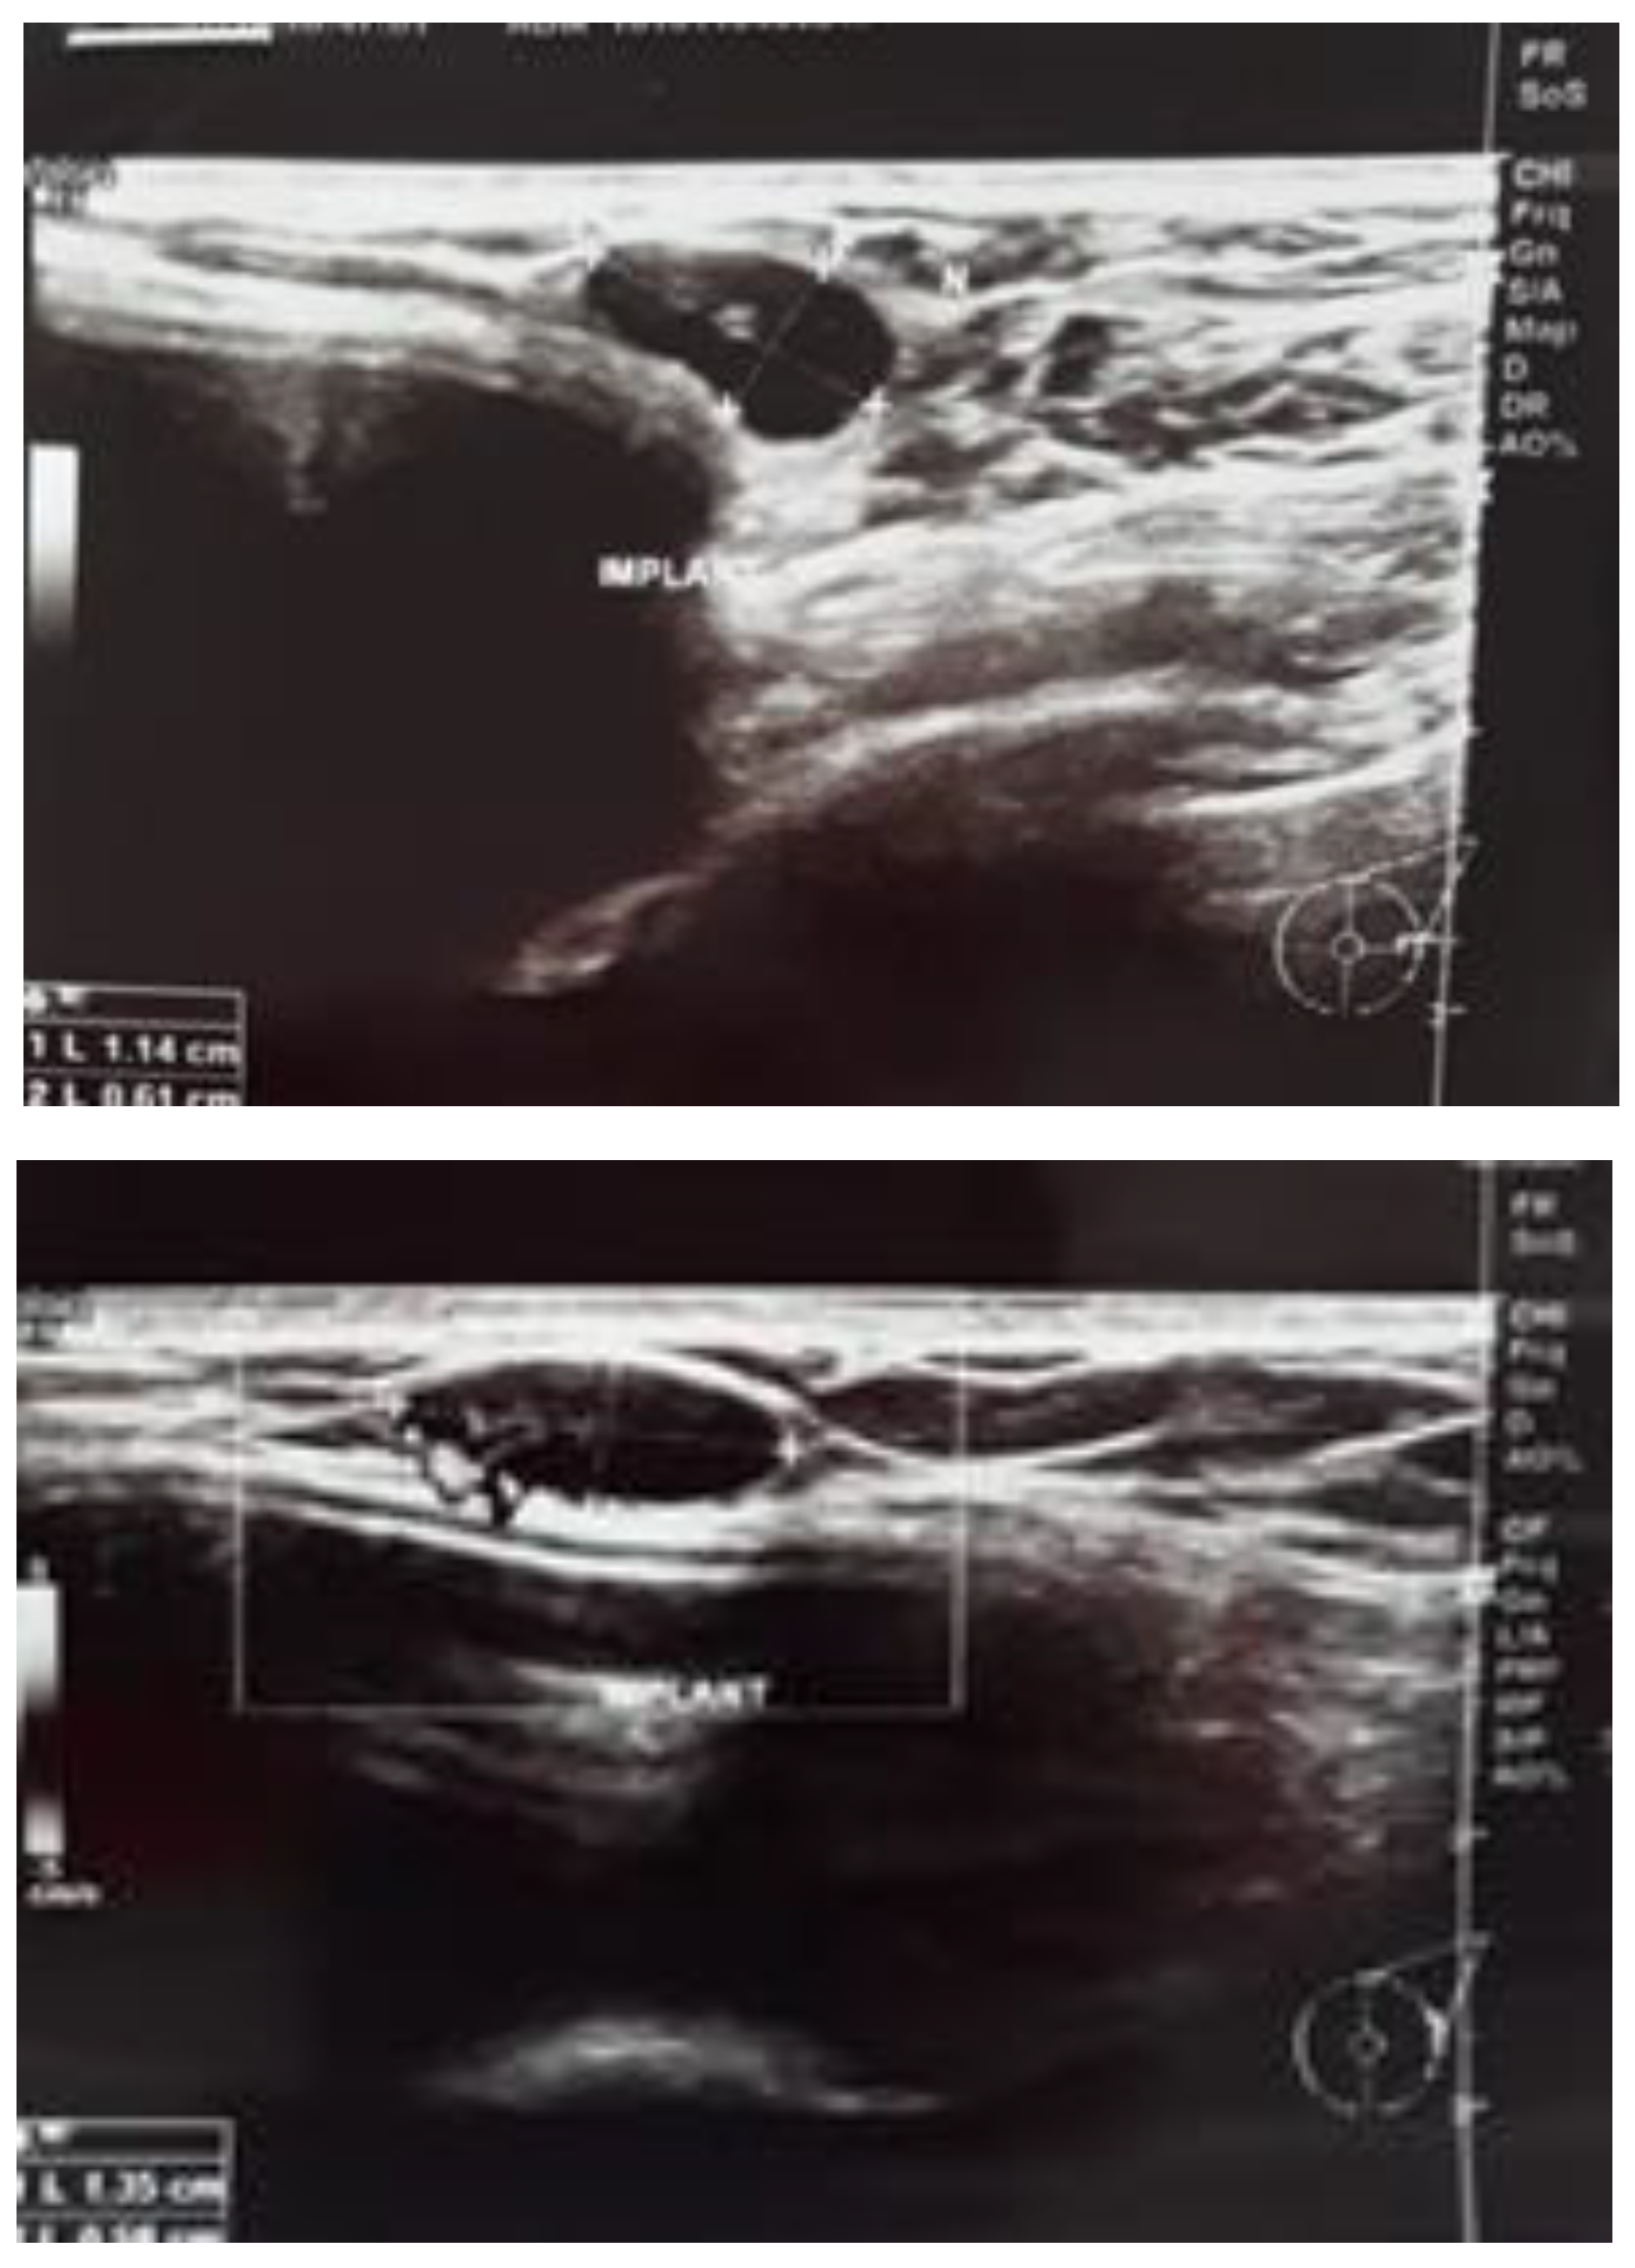

In order to establish the structure and mobility of the tumor, a mammary ultrasound was performed describing a 1.35/0.58 cm lymph node image located at the periphery of the external breast pocket, near the implant, with increased vascularization, smooth contours, and mobile from adjacent planes (Figure 2).

Figure 2.

(a,b). Mammary ultrasound showing a lymph node image located at the periphery of the external breast pocket.